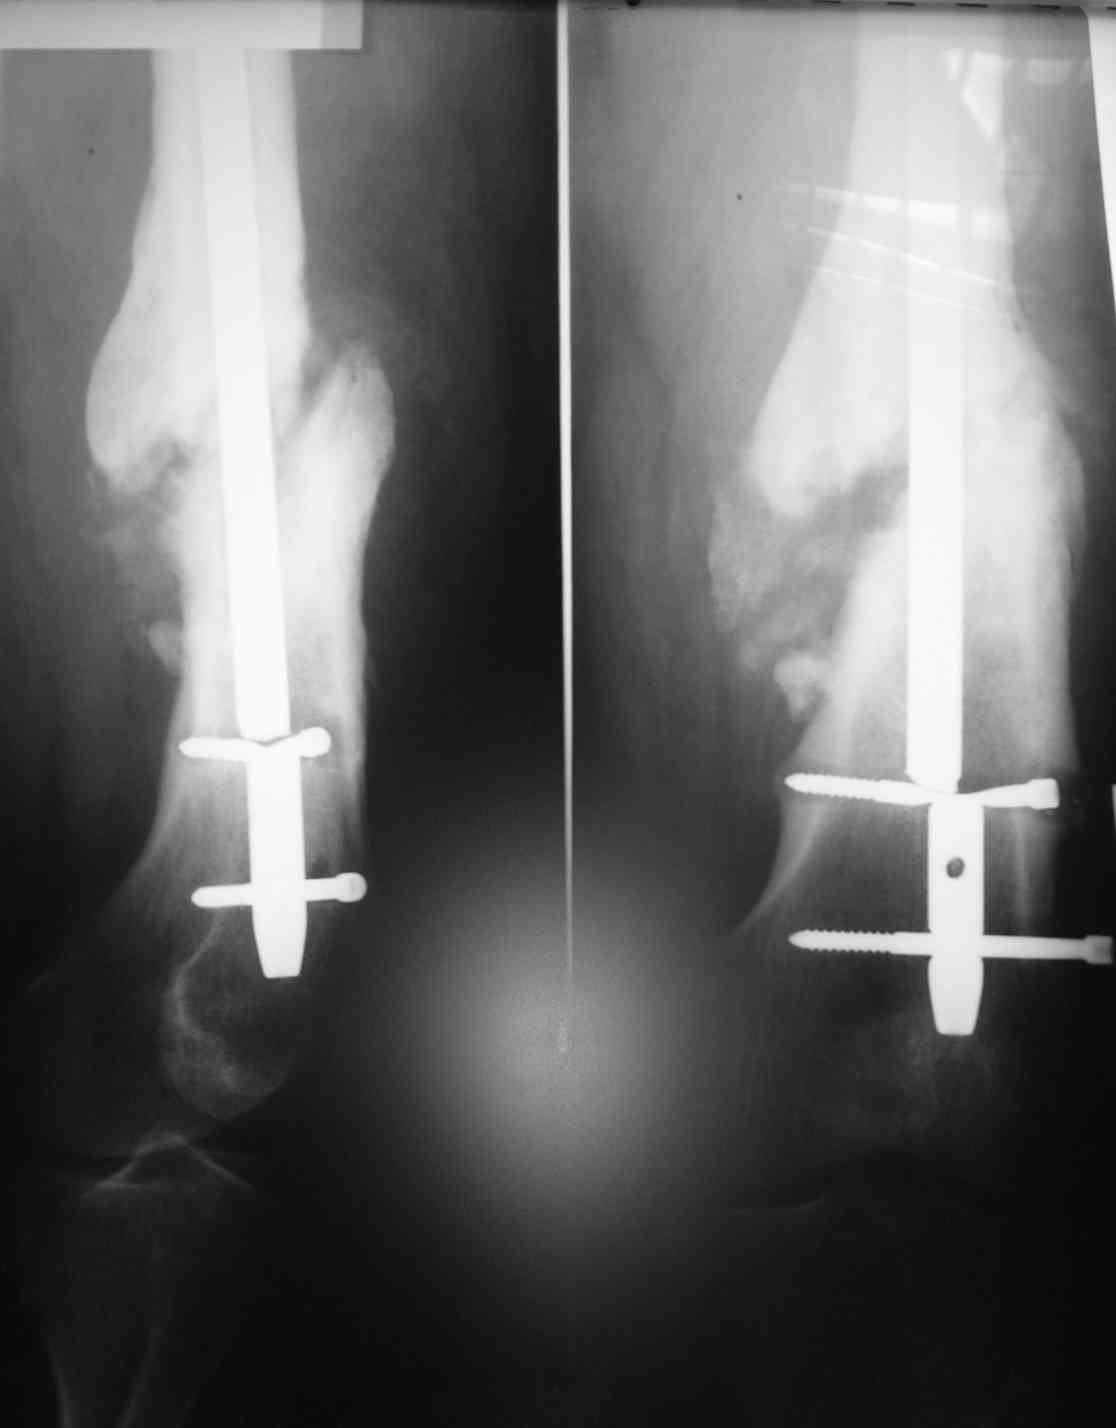

Обратился мужчина, 120 кг, из анамнеза: 1.5 года назад была проведена операция установка антеграднего стержня в связи с переломом в дистальном отделе бедренной кости. Спустя 1.5 года - несросшийся перелом кости и перелом стержня. Регулярно травматологом не наблюдался. недавно обратился к травматологу из-за возникшей боли. Посоветуйте, как наиболее доступно и наименее травматично удалить эту конструкцию? Тактика дальнейшего оперативноголечения?Мы планируем после удаления старой конструкции, установку ретроградного бедренного стержня с рассверливанием и первичной динамизацией. С Уважением,Семенов Евгений

ЕС> года - несросшийся перелом кости и перелом стержня.

А динамизировали стержень? Есть сейчас снимок верхнего конца?